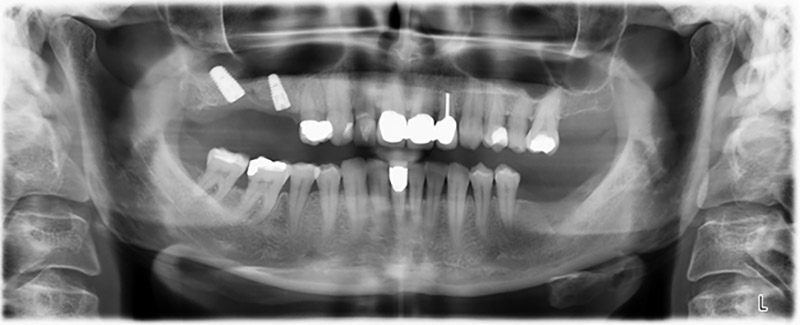

Al fine di pianificare e minimizzare i rischi, circa sei mesi dopo l'estrazione dei denti 16 e 14 viene effettuata una tomografia digitale volumetrica (DVT, Planmeca), la quale conferma chiaramente la mancata rigenerazione ossea nel volume desiderato (da fig. 2 a 7).